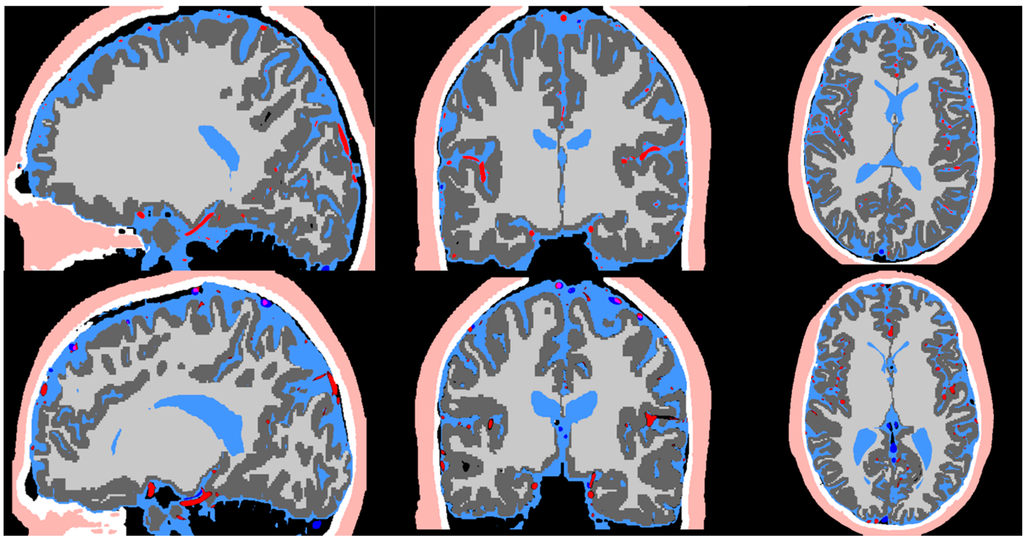

Figure 2 exhibits the MR imaging studies from both subjects in axial, sagittal and coronal views respectively. The maximum intensity projection is used for the MRA to better delineate the vessels. The imaging protocols inherently brighten grey and white matter in T1, cerebrospinal fluid space in T2, arteries in MRA, and veins in MRV. The scalp exhibits high intensity in both T1 and T2. The skull does not exhibit any signal in all imaging studies. Image registration was performed to compensate for the different resolution and slice settings in each imaging protocol. Figure 3 shows the registered and segmented results with red being arteries, dark blue being veins, dark grey for grey matter, light grey for white matter, light blue for cerebrospinal fluid space, white for skull, and flesh color for scalp. Figure 3 shows that the coregistration successfully aligned the different structures together.

Figure 3.

Image co-registration of the T1, T2, MRA, and MRV. The registered image is used in the pipeline for segmentation of the scalp (flesh color), skull (white), CSF (light blue), arteries (red), grey matter (dark grey), white matter (light grey), and veins (dark blue).